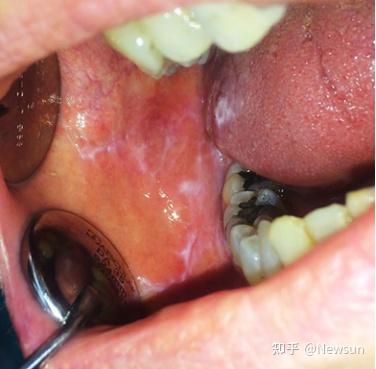

口腔扁平苔藓是一种常见的非传染性、慢性炎症性疾病,主要影响口腔黏膜,如颊部、舌头和牙龈。其确切病因尚不清楚,可能与免疫系统异常、遗传因素、压力或某些药物有关。

症状:患者常出现白色网状、条纹状或斑块状病变,有时伴有糜烂、溃疡或疼痛,尤其是在进食辛辣食物时。少数病例可能演变为癌变,因此定期随访很重要。

诊断:通常通过临床检查和活检确诊,医生会评估病变特征并排除其他疾病。